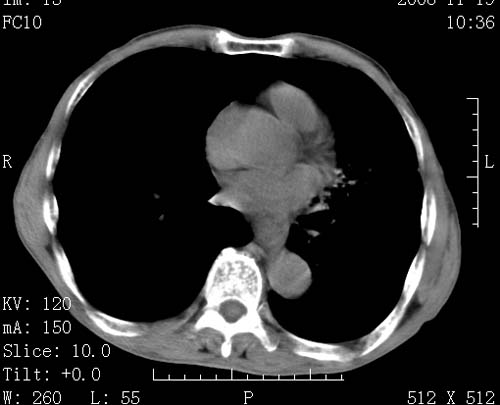

标题: CT16691:m 67 胃镜确诊食管下段及贲门癌 [打印本页]

标题: CT16691:m 67 胃镜确诊食管下段及贲门癌

术前查体,双肺部结节是转移?结核?请点评

1)符合食管癌表现。2)两肺及纵隔淋巴结多发性转移瘤。3)左肺上叶舌段及两肺下叶炎症感染。

1)符合食管癌表现。2)两肺及纵隔淋巴结多发性转移瘤。3)左肺上叶舌段支气管扩张伴感染.

食管癌伴双肺转移,评述:肺部毛细血管网丰富,全身血液均快速流经肺部,癌细胞容易过滤定植,形成转移瘤,影象特点为以毛细血管末梢为中心的结节灶,边缘光滑锐利,少见有中心空洞着,不同来源的转移瘤可有各自特点,如甲状腺癌为双肺弥漫性微结节,本例有原发灶,双肺影象灶典型,左肺舌段条带状网格样伴胸膜天幕征,可视为癌性淋巴管炎。

左肺舌段有斑点钙化灶,能否说明是结核而不是转移?如果是转移将放弃手术改成化疗,如果是结核将考虑择期手术